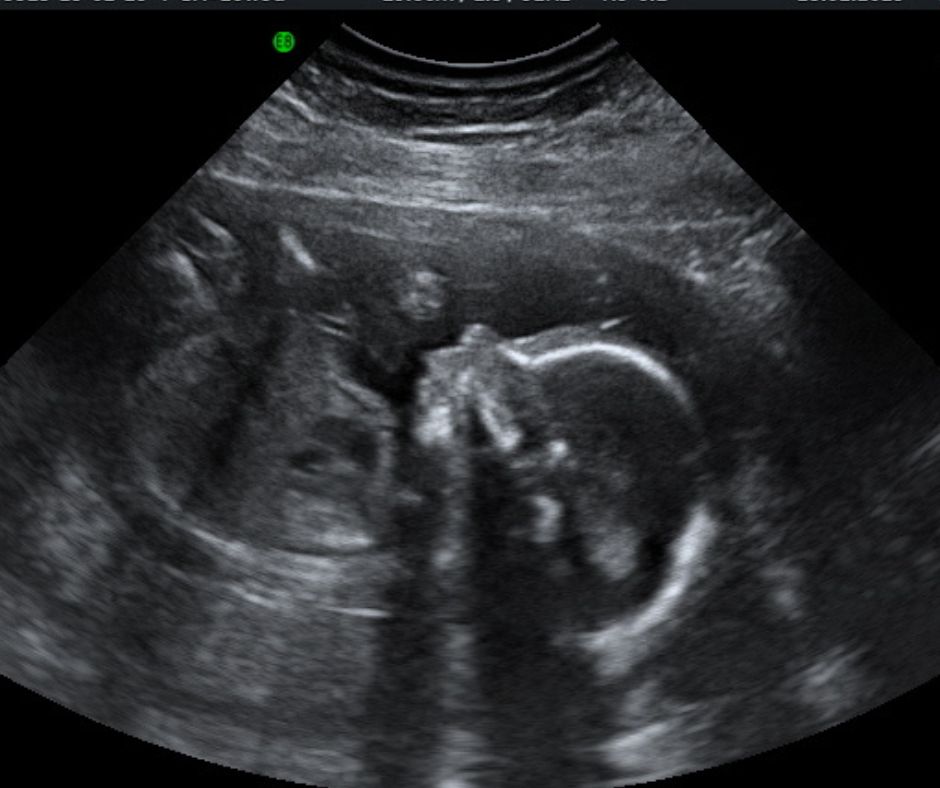

2D Reassurance Scans

2D Reassurance Scan Only £55.00

2D Reassurance scan this is to check the well being of your baby

This scan is available from at least 18 weeks to no more than 24 weeks, is designed to give you a reassurance it include:

The quality of the visual result of the scan is dependent on the stage of pregnancy, the size and position of the baby, the volume of amniotic fluid and the amount of tissue (skin, muscle, etc) between the ultrasound probe and the foetus in the womb. A good image cannot always be obtained.